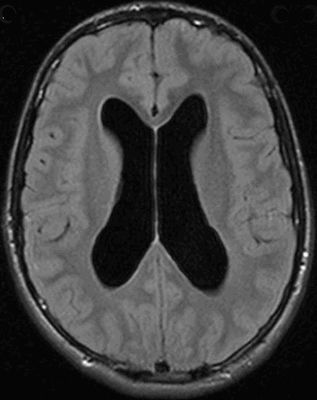

МР-снимок церебральных структур в режиме Т2 (аксиальная проекция)

Анализ результатов МРТ головного мозга заключается в расшифровке снимков, выполненных в трех плоскостях (аксиальной, сагиттальной и коронарной) с шагом среза от 1 мм. Сканирование области интереса проводят в разных режимах. Основными являются Т1 и Т2 ВИ. Отличие режимов друг от друга состоит в отображении структур, содержащих жидкость. Ткань с большим количеством воды в режиме Т1 имеет на фото темную окраску, в Т2 - светлую. По-разному выглядит серое вещество головного мозга. В последовательности Т2 субстанция визуализируется в светлом оттенке.

МР-снимок головного мозга в режиме Т1 (аксиальная проекция)